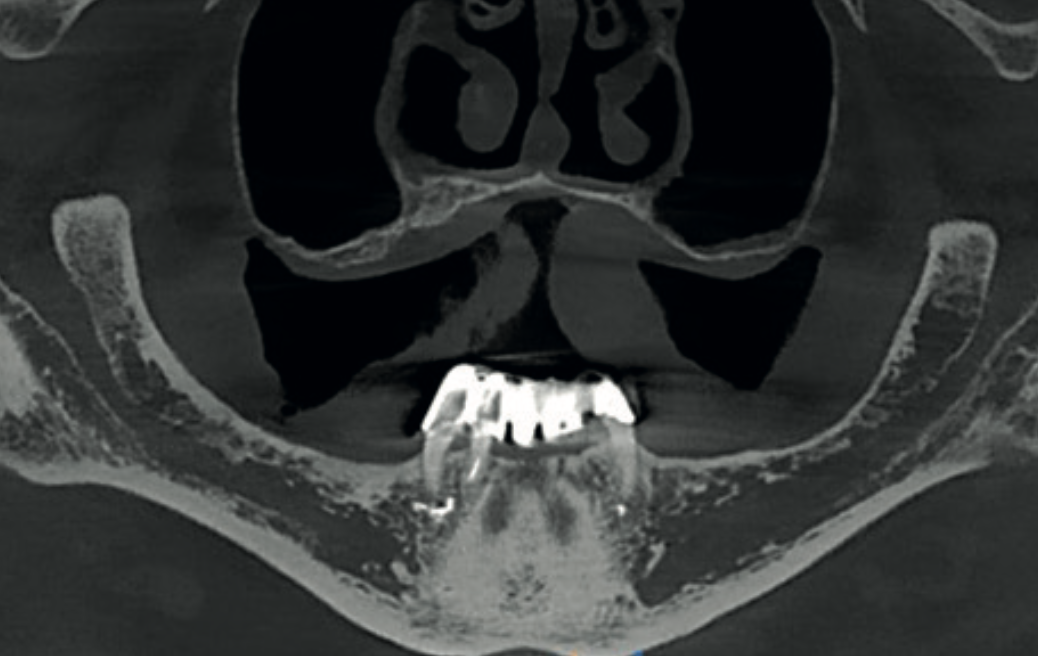

Reformatted panoramic CBCT view showing edentulous maxilla and three remaining mandibular teeth

Fig. 1 Reformatted panoramic view from the CS 9600 showing the edentulous maxilla and three remaining mandibular teeth supporting a fixed prosthesis.

A 65-year-old male with an unremarkable medical history was referred for a CBCT scan before planning implant placement. He was fully edentulous in the upper jaw. In the mandible, only three teeth remained — the lower right canine, lower right lateral incisor, and lower left canine — all endodontically treated and supporting a fixed bridge.